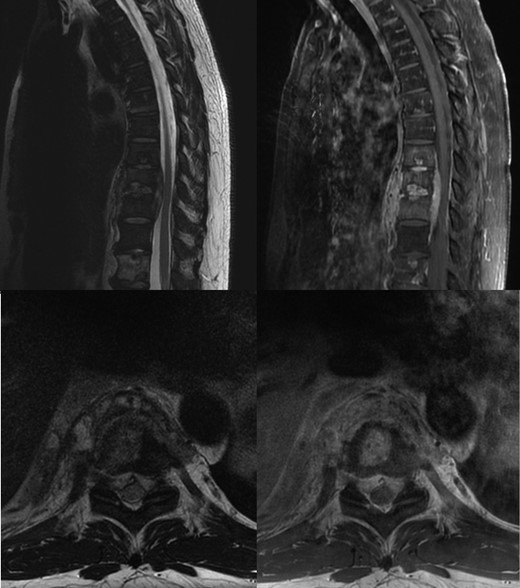

During this period he also developed osteolytic lesions of the T9/10 vertebral bodies immediately adjacent to the effusion (Fig. 1). Magnetic resonance imaging (MRI) was arranged showing T8–T10 spondylodiscitis, prevertebral and epidural phelgmons (Fig. 2), without radiological evidence of spinal cord compression. Further imaging with gallium scan showed no evidence of osteomyelitis elsewhere in the body, but unexpectedly revealed area of increased vascularity in the right iliac fossa suggestive of soft tissue infection. CT abdomen confirmed the lesion to be a peri-appendicular abscess (Fig. 3).

Non-contrast T2 and post contrast T1 MRI, showing T8–T10 spondylodiscitis, prevertebral and epidural phelgmons, without radiological evidence of spinal cord compression.